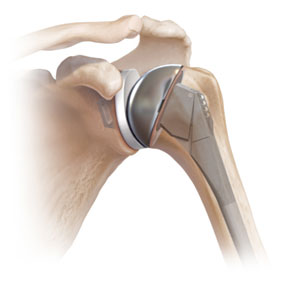

Numa artroplastia total de ombro normal ou “anatómica”, a cabeça do úmero e a glenoide são substituídas de modo a imitar a anatomia e a mecânica natural da articulação do ombro.

A cabeça do úmero ou “ball” é substituída por um implante de metal feito de crómio-cobalto e titânio que se assemelha ao tamanho e anatomia nativos da cabeça. A glenoide ou “socket” é substituída por polietileno (plástico) que é semelhante em tamanho e forma à anatomia natural da glenoide.

Este procedimento é normalmente indicado para pacientes com artrose do ombro que possuem tendões da coifa dos rotadores intactos ou normais (fig. 1).